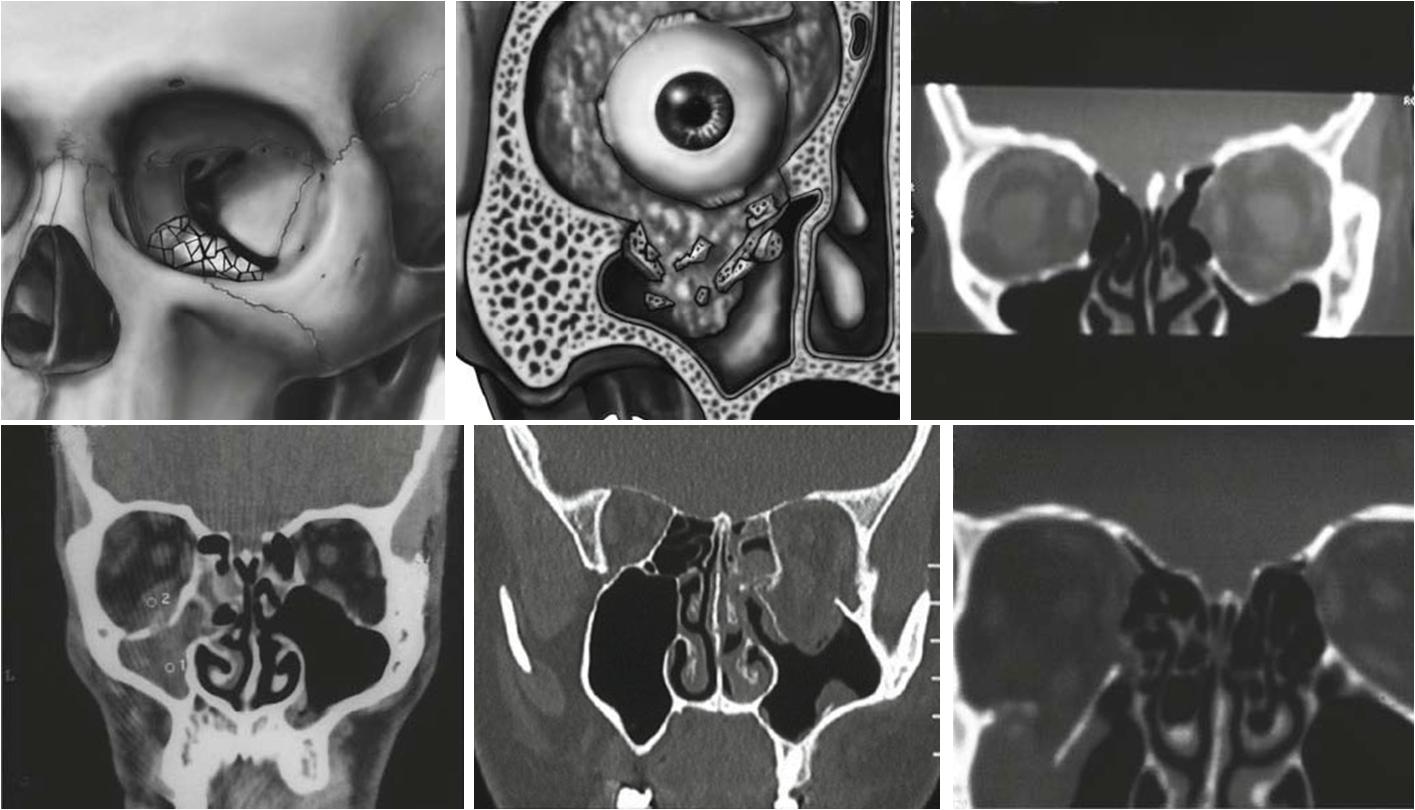

眶底骨折较弱,主要由上颌窦上壁的眶突所组成。眼眶底部是从后面延伸的斜面。眶底后部为眶下管及眶下裂隙较弱。这个区域连接到筛孔纸板上,形成眶下壁,薄如纸张。正中面受外力冲击时,会造成眶底受压增大,造成眶底骨折。这类断裂也称为喷射断裂。因为上颌窦位于眶底以下,眶底骨折往往会导致眶内内容物疝入上颌窦。

眶骨是包含眼球的骨腔,眼球大致呈金字塔状,眶尖位于锥体顶部。眶骨由颧骨,筛骨和其他7块骨组成。眼窝底部主要由上颌,颧骨和上颚构成。眼眶前后由上颌骨、泪骨、筛骨和蝶骨构成。它的主要结构是0.2-0.4 mm厚的筛板。眶壁的解剖结构最为复杂。眶底部和内侧壁是最常见的骨折部位。

3、骨折分类

眼眶边缘完好,只有眶壁骨折;非单纯性眶内壁骨折:眼眶边缘、眶壁复合骨折,多为颧骨复合体、眶筛骨、额骨复合骨折。

3、CT检查

通过对轴位、冠状位及三维重建 CT图像的分析,可以明确眶缘、眶壁骨折及软组织损伤的具体情况,选择手术适应证,指导手术方案的制定。